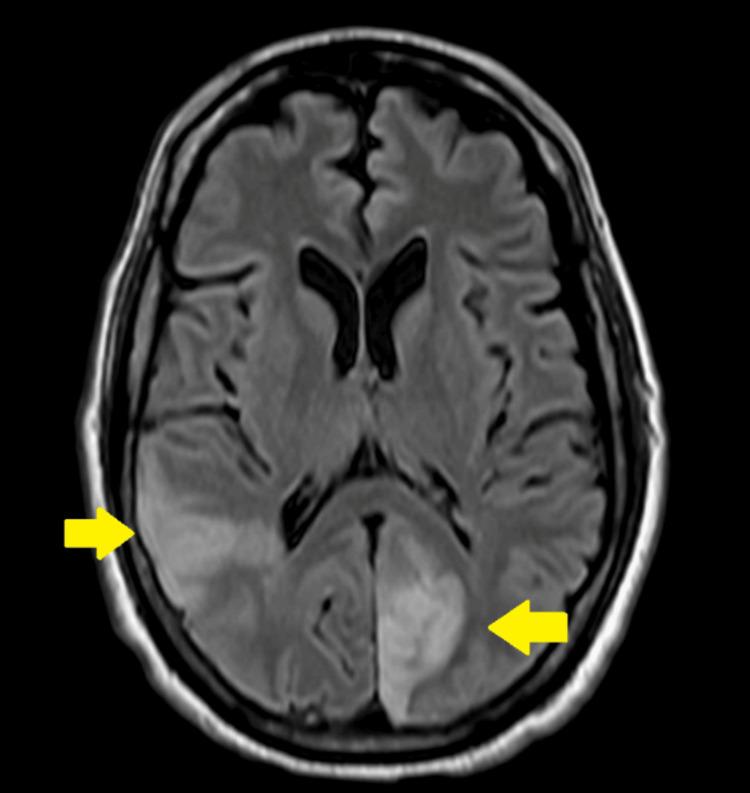

Endocarditis involves inflammation of the inner layer of the heart, known as the endocardium. This condition typically presents with vegetation, with bacteria and fungi usually being the primary culprits. It is divided into two main categories based on its cause: infectious endocarditis and noninfectious endocarditis (NIE). Most cases of NIE are associated with malignancies, most of which are adenocarcinomas of the pancreas and lungs. We present the case of a 63-year-old man with recently diagnosed stage 3 non-small cell lung cancer and a previous history of thrombosis to the renal and popliteal arteries alongside an extensive cardiovascular history who presented with blurry vision secondary to multiple acute ischemic strokes, initially thought to be a consequence of septic emboli due to bacterial endocarditis; however, further workup revealed otherwise, illustrating the complex relationship between malignancy and endocarditis and its ramification.

心内膜炎累及心脏内层,即心内膜的炎症。这种病症通常表现为赘生物,细菌和真菌通常是主要病因。根据病因,它主要分为两类:感染性心内膜炎和非感染性心内膜炎(NIE)。大多数NIE病例与恶性肿瘤相关,其中大多数是胰腺和肺部的腺癌。我们报告了一例63岁男性患者,最近被诊断为3期非小细胞肺癌,既往有肾动脉和腘动脉血栓形成史以及广泛的心血管病史,因多发性急性缺血性中风出现视力模糊,最初认为是细菌性心内膜炎导致的脓毒性栓子所致;然而,进一步检查结果并非如此,这说明了恶性肿瘤与心内膜炎之间的复杂关系及其后果。